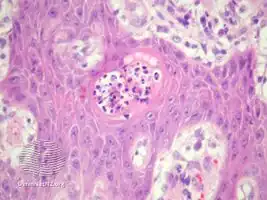

Blastomycosis-like pyoderma is a cutaneous condition characterized by large verrucous plaques with elevated borders and multiple pustules.[2]

Blastomycosis-like pyoderma/pathology